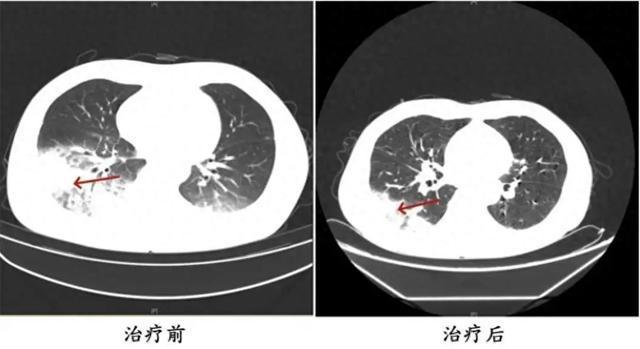

周先生治疗前后肺部CT影像

起初,他以为只是感冒,但吃了感冒药都不见效,反而愈发严重。入院之后,胸部CT显示李先生的左肺已出现大面积白色影像,几乎占据肺部一半。经过检测,最终确认是嗜肺军团菌肺炎。

2024年6月,湖南的周先生驾车出差时,因为天气热,启动了久未清洗的车载空调,每天在车上的时间超过十个小时,回来后就出现了和李先生类似的症状。经过检查,同样确诊为军团菌肺炎。